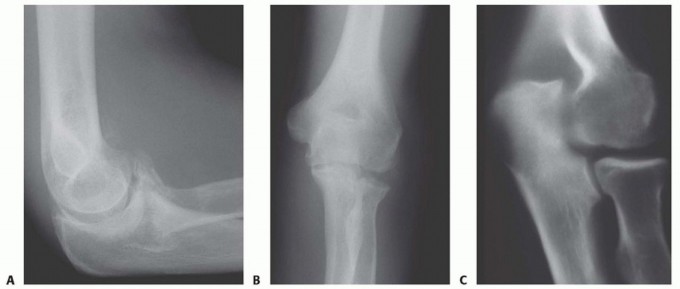

Surgical Management of Traumatic Conditions of the Elbow: Interposition Arthroplasty